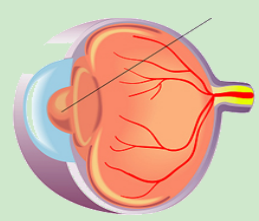

1.png

正常视网膜血管

2.png

糖网的视网膜血管渗漏